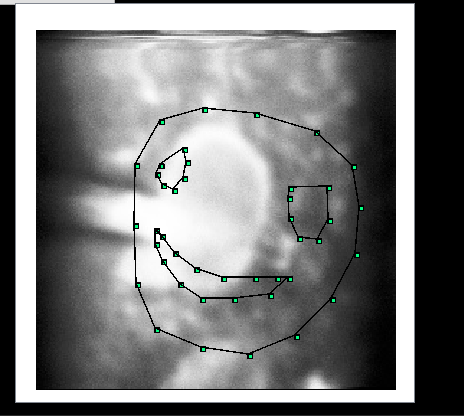

重写试图里面的鼠标事件,获取鼠标点击的坐标,坐标用Qvector容器存起来。设置添加小正方形和直线的图元,不仅能圈出感兴趣的区域,还能标记很多个区域。得到图五:

(图五)